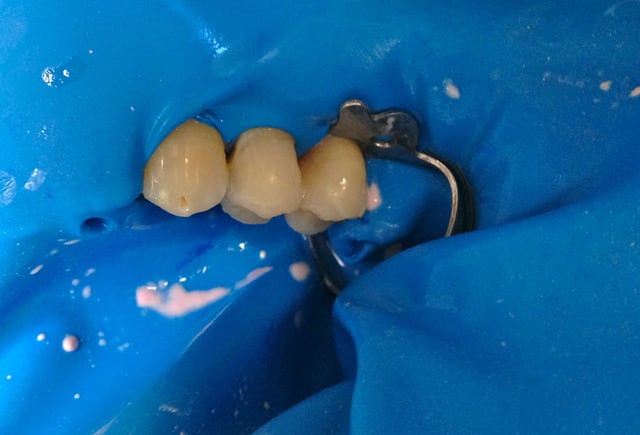

Alors comment traiteriez vous cette 24 asymptotique, qui présente un enorme délabrement sous gingival , notez que l'émail n'est plus soutenu par la dentine à aucun endroit ?

1ère séance remontées de la marche distale au compo flow + compo de restauration / réalisation d'un IDS , le tout sous digue bien sur (voir radio jointe , désolé à l'envers))

Je vous met les photos de la pose de ce matin, par contre désolé pour les puristes , mais photos faites avec un iphone....

Voici les photos toutes fraiches de ce matin.

Vos critiques sont bien sur les bienvenues je dois encore beaucoup m'améliorer sur les prises de teintes, et je m'y attelle en ce moment,, par contre en ce qui concerne la pérennité de la restauration…..ma patiente a sa dent bien vivante, aucun joint sous gingival , possibilité de réaliser une endo dans le futur sans détruire la restauration existante si besoin, possibilité re refaire un onlay dans quelques années si ça casse, toujours sur dent vivante…. bref la liste des avantages est très longue par rapport au classique endo-IC-CCM.